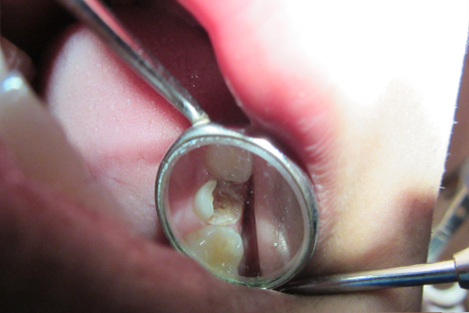

Dental Dam Isolation